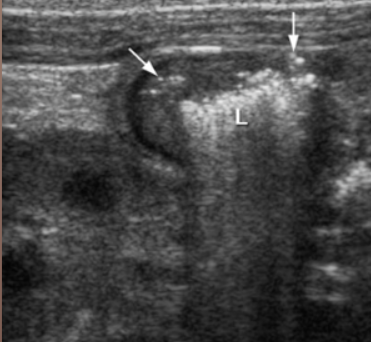

Acute appendicitis